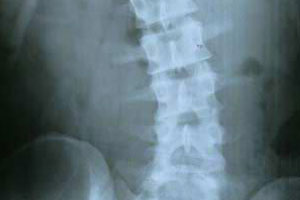

腰椎间盘突出主要是由外因、内因、椎间盘本身退行性变等原因而导致的,腰椎间盘突出给患者带来了很大的困扰。那么,腰椎间盘突出症的治疗方法有哪些呢?下面我们一起来了解。

腰椎间盘突出: